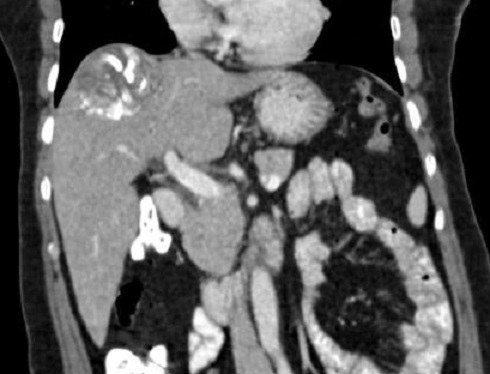

|

Image TDM d'une abces du foie en coupe

coronale . Aspect de la lesion est hypodense

multi loculaire se situe au foie gauche . Image

radiologique TDM encoupe coronal , aspect

radiologique en susgeste du abces a pyogenes |

Image radiologique TDM d'une abces

amibien du foie droit avec aspect lesionnel est un masse

hypodensite a paroi epaise attenue et zone de

oedemateuse hypodense peripherique

Image radiologique TDM d'une grande abces amibien du

foie gauche avec aspect lesionnel est une masse

unique, arrondie 10 cm de

diamètre hypodense sur TDM avec

rehaussement de contraste périphérique, contours

réguliers . Image radiologique TDM plus C+ phase

veineuse |